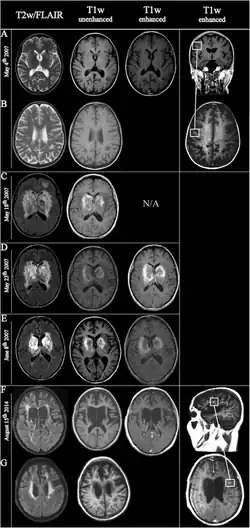

![]() | |

Fulminating ADEM showing many lesions. The patient survived, but remained in a persistent vegetative state | |